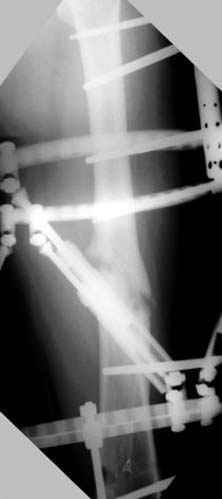

На рисунке N1 предоперационный план лечения ложного сустава шейки бедра- линия ложного сустава, угол и направление введения импланта, клиновидная остеотомия в градусах и миллиметрах, второй снимок после коррекции, расчет, на сколько удлиняется конечность и размеры импланта;

N3 рисунок окончательный снимок, после операции моя рентгенограмма должен выглядеть примерно как эта картина. На N4 снимке клин перед удалением; N5 послеоперации 3 нед.; N6 окончательная рентгенограмма.

варус при проксимальном отделе 95 градусной пластиной.